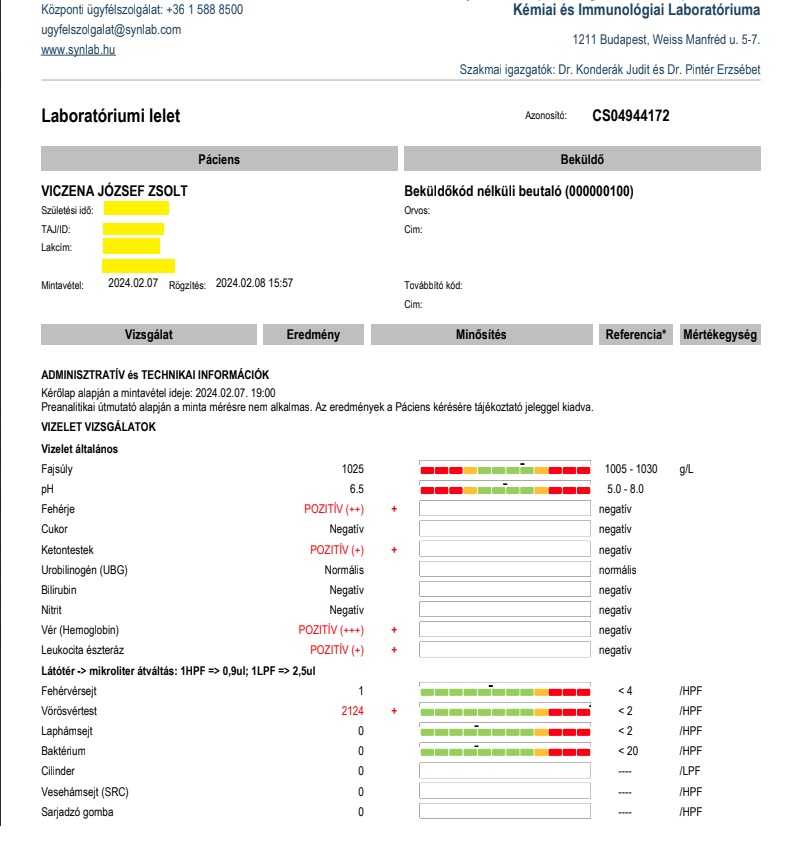

Ezután két nappal, 8-án Zsoltot elöntötte a vér, a vizeletében a megengedett vörösvértest mennyiség több mint ezerszerese volt (!)

Február 8-án leadtuk a véres a vizeletet, melynek eredményét úgy kellett telefonon kikérni, szinte alig adták ki, mert olyan brutális, ezerszeres vérvizelés értékeket (2124 illetve 1286 vörösvértest/látótér) jelzett a vizsgálat, amilyennel szinte nem találkoztak, magánbeteg által leadott mintáknál szinte biztosan nem – mert aki ilyen beteg egyből állami kórházi ellátást kap civilizált országokban. A normális tartomány határa 2 vörösvértest látóterenként, a vizsgálat pedig vér+++, proteinuria ++, ketonuria +, leukocyta észteráz + értékeket mutatott. A Synlab az egyetlen megbízható pont volt számunkra, amely rengeteg vizeletvizsgálatot és egyéb labormunkákat végzett nekünk, rengeteg pénzt kellett otthagynunk.

Visszatérve a mintákra, párhuzamosan leadtunk egy mintát a Synlab-hoz is, kvantifikálja az eredményt ellentétben más leletekkel. Szintén alarm eredmény!